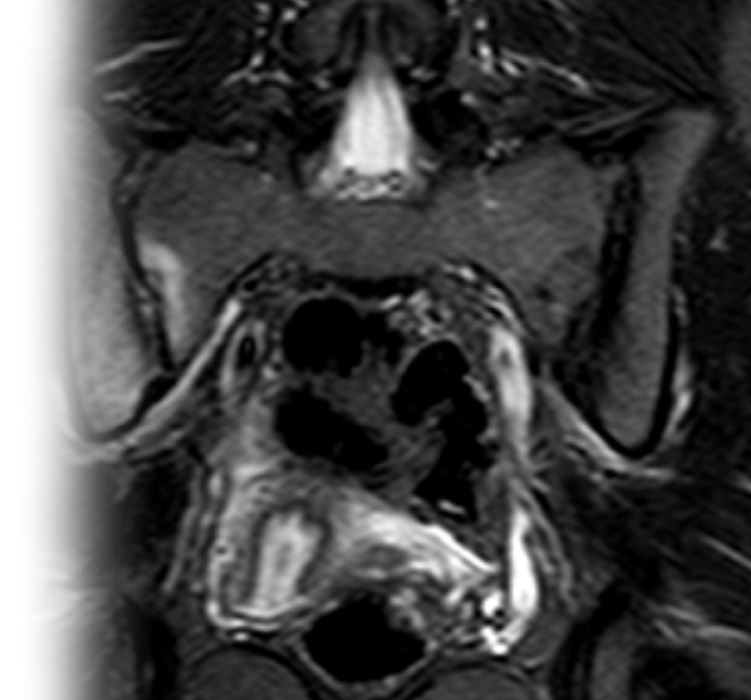

МРТ крестцово-подвздошных сочленений

Магнитно-резонансная томография крестцово-подвздошных сочленений – важный метод исследования, который позволяет оценить состояние крестцово-подвздошных сочленений.